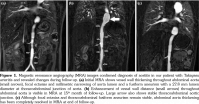

Initial physical examination was normal, including blood pressure and there were no pulse and blood pressure discrepancies among extremities. Acute phase reactants were markedly elevated and autoantibodies were all negative. Viral and bacterial serological markers, interferon- gamma release assay and tuberculin skin test were negative. Abdominal ultrasound, chest X-ray, skin pathergy test and ophthalmological examination were also normal. Renal Doppler ultrasonography revealed diffuse vessel wall thickening and lumen narrowing of renal arteries. Magnetic resonance angiography (MRA) led to the diagnosis of large vessel vasculitis (Figure 1a). Echocardiography also showed vessel wall thickening in the ascendant aorta. Fortunately, carotid Doppler ultrasonography did not reveal stenosis or reduced blood flow, although vessel wall thickening was present in bilateral common carotid arteries.

After TA diagnosis was established, systemic methylprednisolone (2 mg/kg/day) and methotrexate (15 mg/m2 per week) were initiated. Three months later, current therapy did not alleviate the systemic symptoms, so an anti-tumor necrosis factor-alpha agent infliximab (7 mg/kg), was added. After six months, methylprednisolone could be gradually tapered to 0.3 mg/kg per day. One year after the initiation of infliximab, carotid Doppler ultrasonography was repeated due to new onset of carotidynia and revealed diffuse stenosis in bilateral common carotid arteries. Furthermore, MRA showed the fusiform thoracoabdominal aneurysm and progression of abdominal aortitis (Figure 1b). We decided to switch methotrexate to MMF (600 mg/m2/day). Six months later under MMF, infliximab and low-dose of systemic methylprednisolone treatment, MRA showed complete regression of wall thickening in the abdominal aorta (Figure 1c). The laboratory results of the patient were summarized in Table 1.